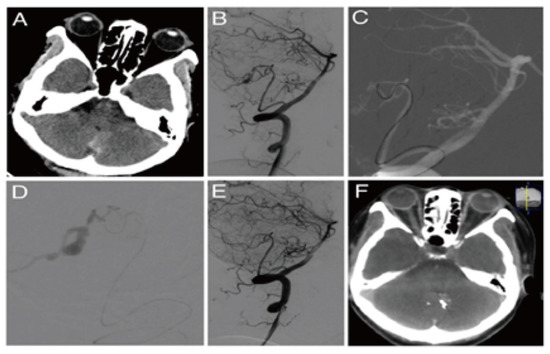

After reviewing 275 patients with 313 PIAs with MMD, Anthony et al. found that 95% of patients treated with endovascular therapy had no or minimal deficit, in contrast to open surgery (69.6%) [21]. The self-healing of PIAs of MMD patients was reported during follow-up [22] or after extracranial–intracranial bypass [19]. Therefore, endovascular treatment for PIAs in MMD should be based on comparing the risk of rebleeding with follow-up or extracranial–intracranial bypass [19]. In our study, there was a dissecting aneurysm located at the distal smoky middle cerebral artery, inaccessible by the microcatheters, which were occluded from the proximal end of its parent arteries, resulting in bilateral hemisphere infarction and herniation (Figure 1). Therefore, we believe that aneurysm occlusion or parent artery occlusion could be performed only if compensatory arteries are small-scale or non-functional, as confirmed by the microcatheter super-selective angiography [23]. Otherwise, extracranial–intracranial bypass should be considered [18].

Figure 1. Moyamoya disease with a peripheral hemorrhagic aneurysm. (A) Preoperative CT revealed periventricular and ventricular hemorrhage. (B) Left internal carotid arteriography revealed smoky vascular hyperplasia with a false aneurysm at the end of the lenticulostriate artery. (C) The parent vessels were too tortuous and slender for super-selection. A Marathon microcatheter was located at the beginning of the parent artery. (D) Glubran was used to block the parent artery with satisfactory diffusion to the distal aneurysm cavity. (E) After the embolization, the aneurysm and parent artery disappeared on arteriography. (F) Postoperative CT revealed that the position of the glue coincided with the location of a brain hemorrhage.